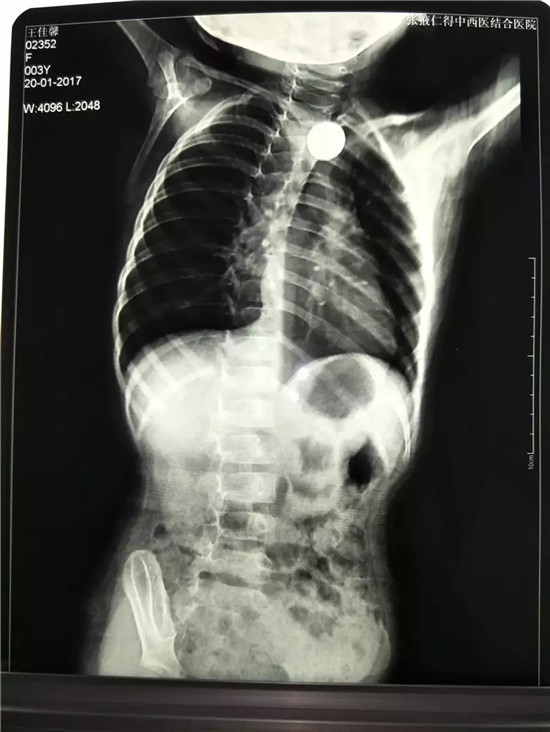

胸片顯示:食道上段可見一異物

硬幣卡在食道入口下方約1.5cm處

????1月20日16:00,一名3歲小孩在家屬的匆忙腳步聲中來到河西學(xué)院附屬張掖人民醫(yī)院內(nèi)鏡中心。在醫(yī)生的詳細詢問下,最終確定,小孩是誤食硬幣導(dǎo)致的消化道堵塞。由于小孩還不足3歲,消化道尚在發(fā)育中,因此硬幣就卡在了她的食管內(nèi)。初診醫(yī)院胸片顯示:食道上段可見一異物,考慮到孩子年齡太小,不敢進行處理,才轉(zhuǎn)入河西學(xué)院附屬張掖人民醫(yī)院進行治療。

內(nèi)鏡中心護士長王彩虹遂上報醫(yī)務(wù)科、消化科及麻醉科,積極協(xié)調(diào)相關(guān)人員。于16:30分,內(nèi)科主治醫(yī)師曹金灘、麻醉科副主任脫立雄在內(nèi)鏡室護士長王彩虹及主管護師張宏梅、彭云等的配合下,在靜脈麻醉下行內(nèi)鏡下異物取出術(shù)。進鏡順利,硬幣卡在食道入口下方約1.5cm處,遂用鱷嘴異物鉗牢牢夾緊硬幣,通過管道小心翼翼地把硬幣取了出來,前后僅用10分鐘就解決了問題,通過胃鏡觀察小孩的食管壁,沒有發(fā)現(xiàn)損傷、出血,在場的醫(yī)護人員都松了口氣,孩子從入院到出院還不到一個半小時?!⊥ㄟ^內(nèi)鏡下微創(chuàng)治療,既避免了開胸手術(shù)帶來的創(chuàng)傷,解除了患者的痛苦,又節(jié)約了費用。該例微創(chuàng)手術(shù)的成功體現(xiàn)了我院內(nèi)鏡治療水平又上了一個新的臺階。